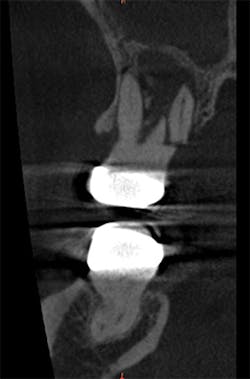

A root fracture, perforated canal, and periapical lesion are all common problems that can appear normal on a 2-D radiograph. Without CBCT imaging, you don't have all of the information necessary to diagnose the issue as superimposition and magnification can make it difficult to see every part of the anatomical structure.

In the past, diagnosing a root fracture was difficult. Based on the patient's description of the pain and a radiograph, a dentist may have prepared the tooth for a crown to see how it felt. When that didn't address the pain, a root canal would have been recommended. After that, the only option may have been extraction. This process was frustrating not only to the patient-who spent time and money to get the pain relieved-but also to the doctor who wanted to address the problem.

Today, we can eliminate this clinical progression by having all of the information upfront. This results in better treatment outcomes and patient care.

Root fracture as seen on an axial scan view. Clinical photos courtesy Dr. Bradley McAllister, DDS, PhD